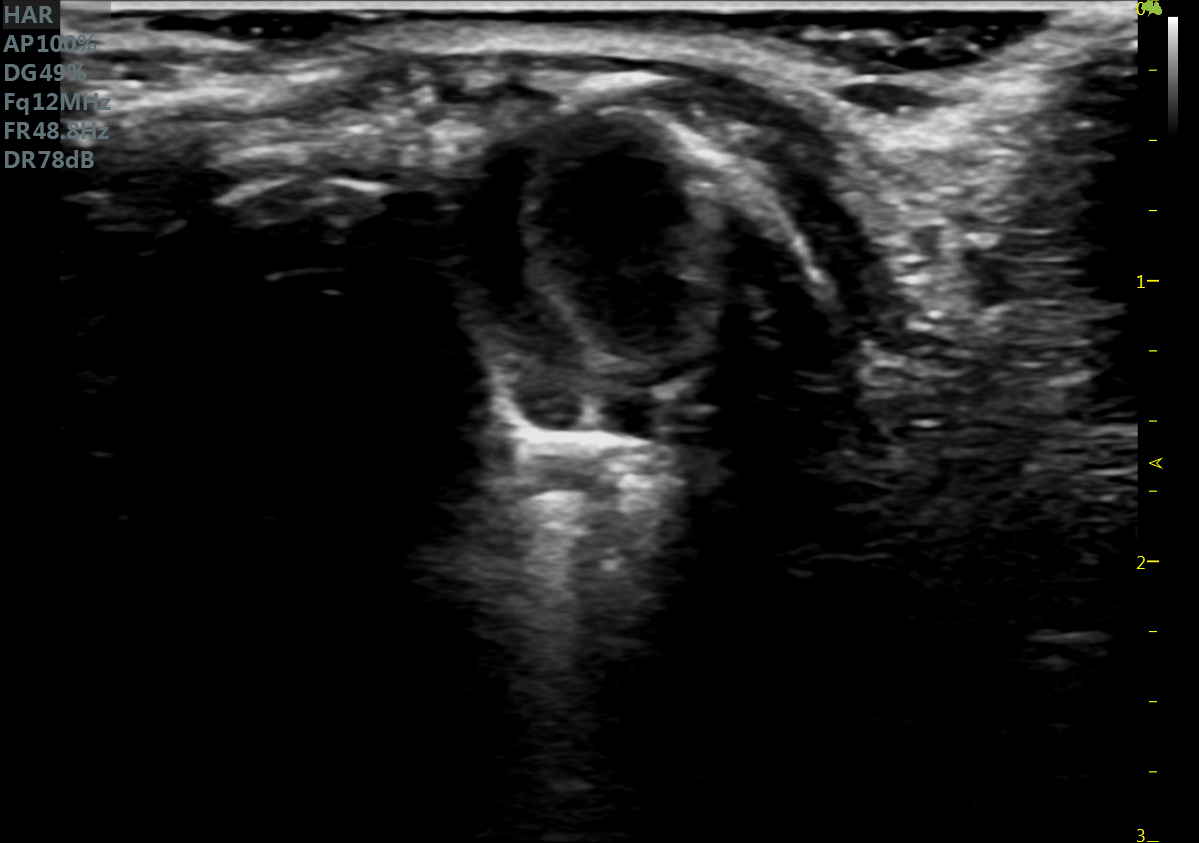

RF Flow充盈不外溢 Xcen超高频浅表显影